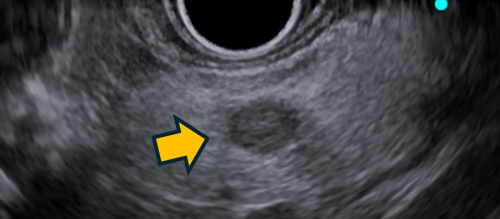

超音波内視鏡ガイド下エタノール注入療法は,超音波内視鏡を使って,腫瘍を確認しながら針で腫瘍を穿刺し,エタノールを注入することで腫瘍細胞を壊死させる治療法です。

超音波内視鏡で描出された膵神経内分泌腫瘍 |

腫瘍穿刺のイメージ |